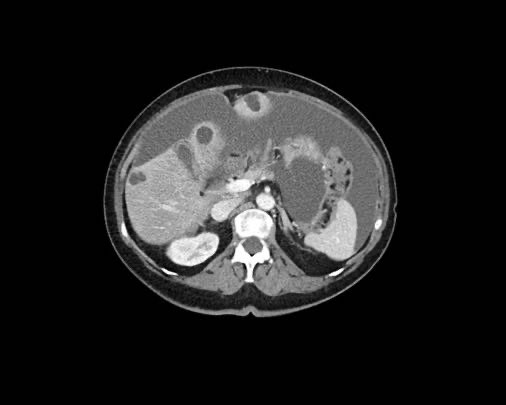

Ca lâm sàng 1

Cuộn qua các lát cắt.

Bạn có thể phát hiện tất cả các tổn thương cấy ghép phúc mạc không?

Bệnh nhân này đã được phẫu thuật và toàn bộ phúc mạc được ghi nhận phủ kín bởi các tổn thương u dạng kê.